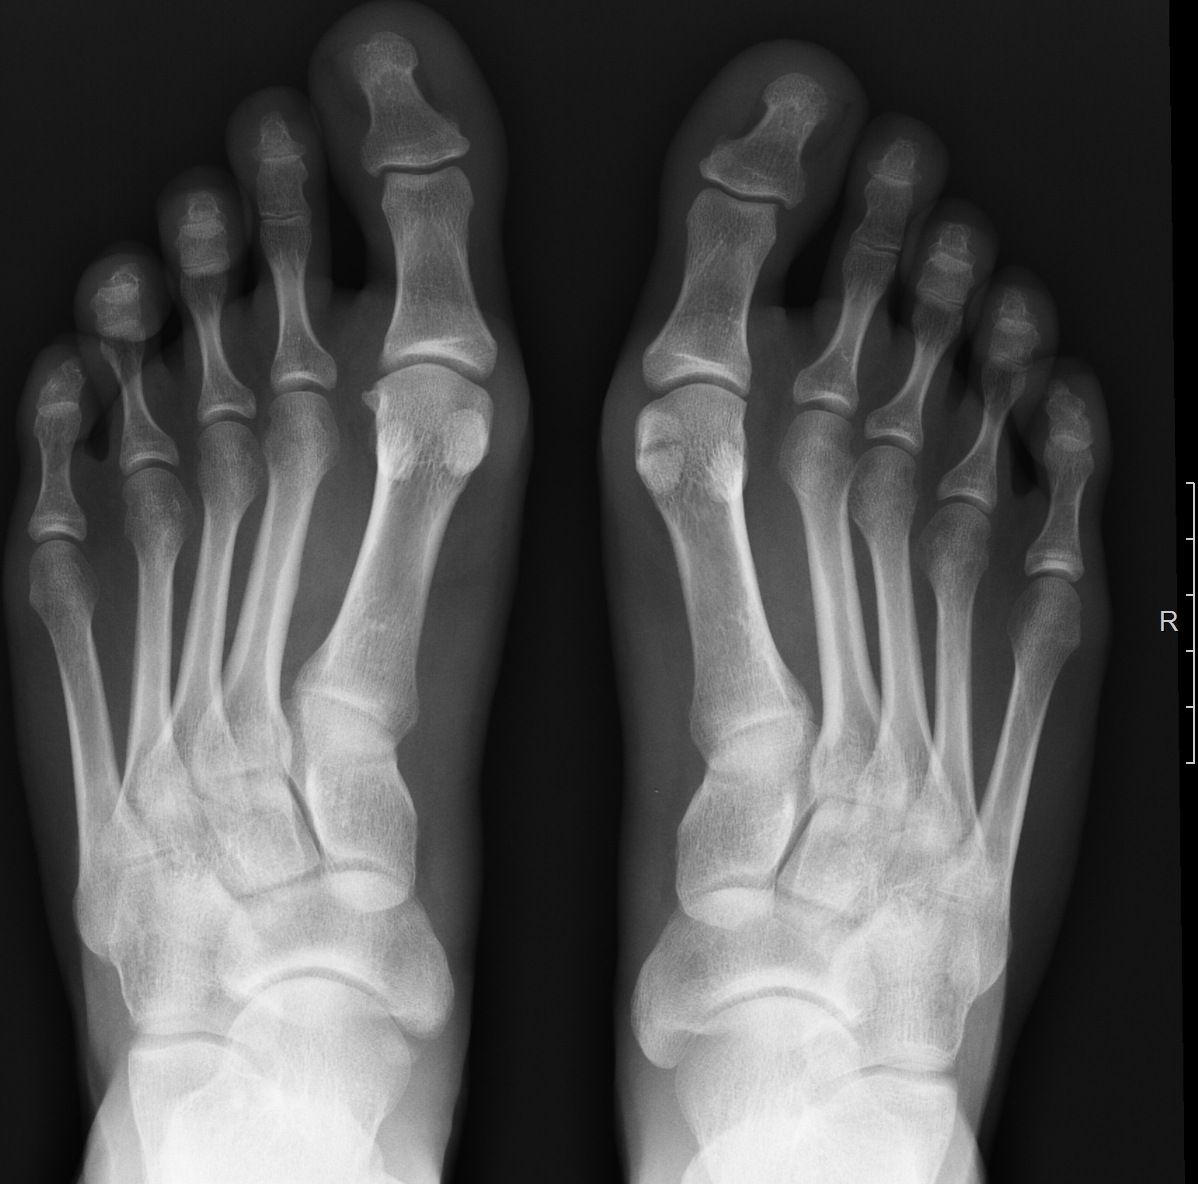

Перелом сесамовидной кости: Визуализация травмы и её лечение